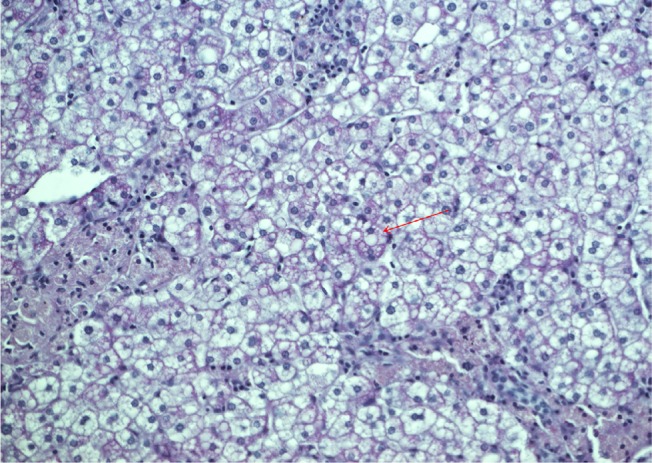

Abstract Image